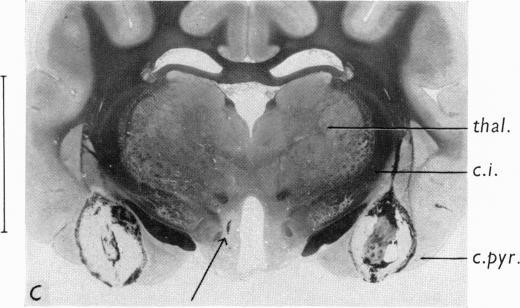

Organization of the subcortical system governing defence and flight reactions in the cat.

J Physiol. 1962 Feb;160(2):200-13. doi: 10.1113/jphysiol.1962.sp006841.